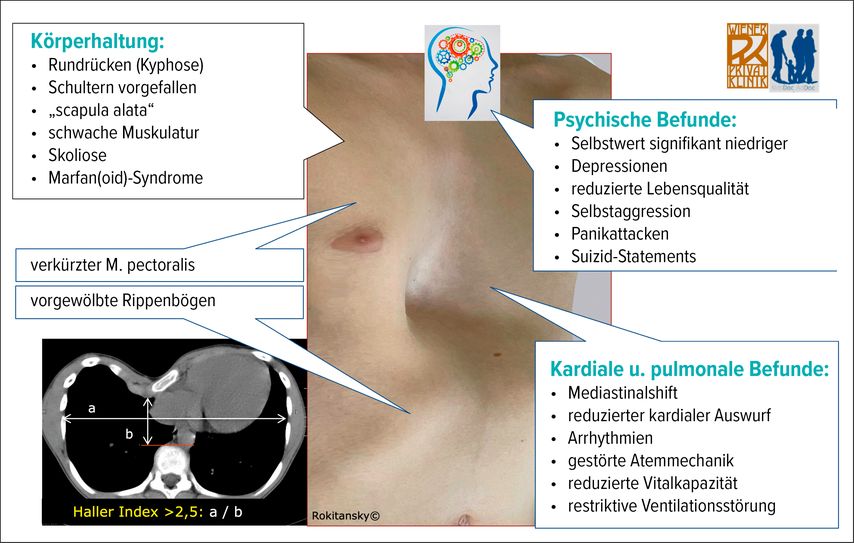

Das Ausmaß der Trichterbrust wird objektiv durch die Bestimmung des Haller-Index auf der Höhe der tiefsten Trichterstelle festgelegt.5 Dabei wird am MRT- oder CT-Schnittbild der transversale Thoraxdurchmesser dividiert durch die sagittale anteroposteriore Distanz zwischen Trichter und Wirbelkörper-Oberflächenebene (physiologischer Normalwert: <2,5; Abb.1 links unten).

Symptomatik

In mittel- bis höhergradigen Fällen kommt es im Zuge des zunehmenden Mediastinalshifts zu einer Linksverlagerung sowie auch einer Kompression des Herzens, wo mechanisch vor allem das rechte Kammersystem betroffen ist.6,7Der rechte Ventrikel ist eingeengt, verliert an Compliance und nimmt in der radiologischen Darstellung eine „tubuläre Form“ an. Damit sinkt auch die „ejection fraction“ und damit insgesamt der „cardiac output“ (Abb.2). Eine Situation, die therapeutisch nachweislich verbessert werden kann.8

Die Lunge kann sich durch die Brustkorbdeformität nicht vollständig ausdehnen, einerseits durch den Trichter, andererseits durch die Dellen-deformierte Insertion des Zwerchfells, das bei maximaler Kontraktion nicht die volle physiologische inspiratorische Entfaltung der Lungen zustande bringen kann. Es resultiert ein atemmechanisches Problem durch das „zu große“, nicht optimal in der Passform abgestimmte und ggf. mit geringerer muskulärer Vorspannung vorliegende Zwerchfell. Eine Situation, die sich nach operativer Korrektur signifikant verbessert.9 Die in der Atemmechanik gestörte Lungenfunktion (FCV) ist um 10–25% eingeschränkt. Dies führt zur Kurzatmigkeit bei körperlicher Anstrengung und kann ggf. auch pulmonale Infektionen begünstigen.

In vielen Fällen führt die Trichterbrust zu nachgewiesenen organischen und psychischen Beeinträchtigungen. Es resultiert, neben einer verminderten Lebensqualität, eine Lebenssituation mit verminderter physischer Leistungsfähigkeit, Schmerzen und einem lokalen Druckgefühl im deformierten Brustkorb. Letzteres ist vor allem im Zuge der Wachstumsphasen zu beobachten.

Die psychische Belastung durch die missgebildete Brust führt bei 80% der Betroffenen zu einer erheblichen Minderung des Selbstwertgefühls und beeinträchtigt die Lebensqualität. Sie kann zu sozialem Rückzug, verminderter Leistungsfähigkeit und depressiver Verstimmung führen. Jugendliche wollen zum Beispiel im Sommer nicht mehr schwimmen gehen und halten ihren Oberkörper gerne vollständig bekleidet. Ein systematischer Review identifiziert soziale Nachteile, depressive Tendenzen, erhöhte soziale Angst, niedrigeren Selbstwert und introvertiertes Verhalten bei Betroffenen im Vergleich zu normierten Populationen.10 Dabei korreliert der psychologische Stress nicht direkt mit der objektiven Schwere der Deformität, sondern eher mit der persönlichen Wahrnehmung und dem sozialen Kontext.10–12 Die komplikationslos verlaufene operative Korrektur hebt die Lebensqualität sowie das Selbstwertgefühl und die Teilhabe an sozialen Aktivitäten, Körperakzeptanz und psychosoziale Gesundheit werden im Durchschnitt signifikant gesteigert.13